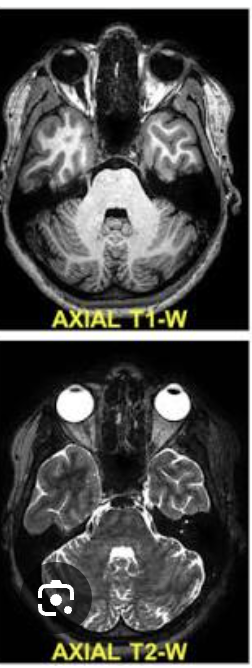

What is MRI?

A cross-sectional imaging technique using a magnetic field and radiofrequency signals to generate images from hydrogen nuclei in water molecules

How are axial MRI images viewed?

From the feet toward the head like CT

What are the two common MRI sequences?

T1-weighted and T2-weighted

What is a basic tenet of MRI?

Define anatomy (T1)

Detect abnormal fluid (T2)

Hint: H2O → T2

White = edema in photo

How does water or edema usually appear on T2-weighted MRI?

Bright